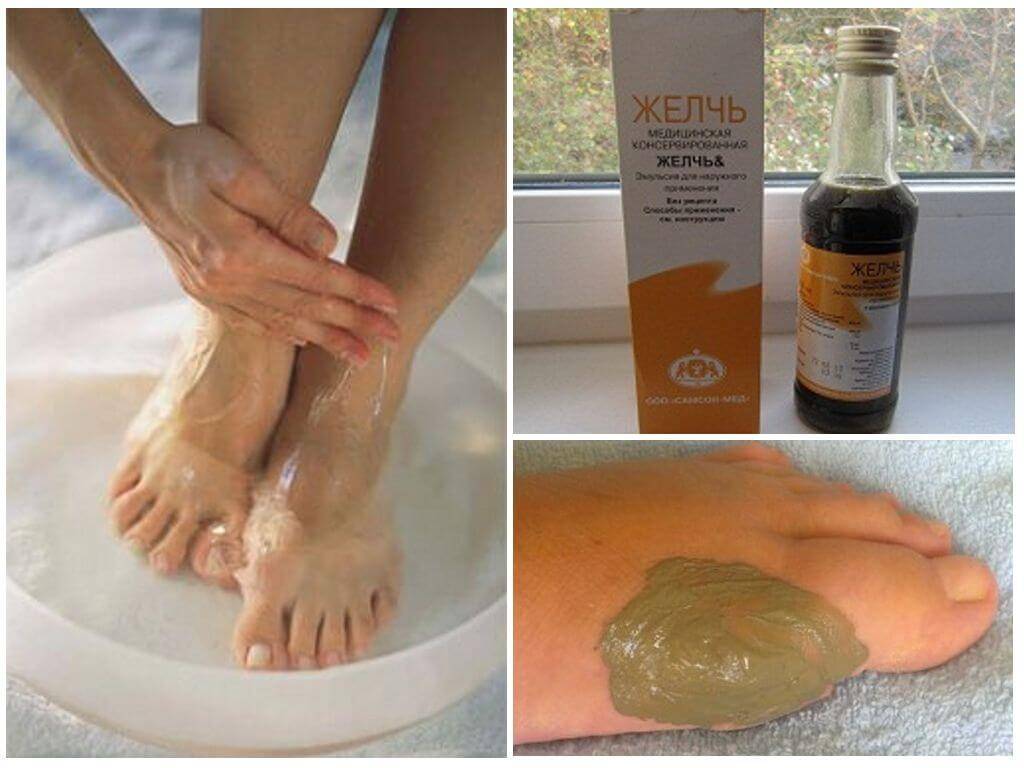

Регулярно делайте теплые ванночки для ног с добавлением морской соли или эфирных масел для снятия воспаления.

Применяйте компрессы с лечебными мазями или гелями для снятия отечности и воспаления.